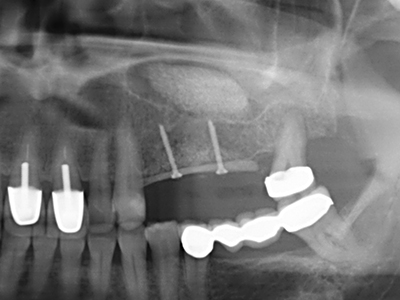

Si es preciso realizar intervenciones quirúrgicas en las que el hueso está en contacto directo con estructuras sensibles, como son los vasos sanguíneos o los nervios, los instrumentos rotativos presentan un enorme potencial de provocar lesiones iatrogénicas. Así, precisamente en la representación de nervios después de una lesión iatrogénica, o en el transcurso de la lateralización de un nervio para resecciones, reconstrucciones o incorporación de implantes, los equipos piezoeléctricos pueden resultar muy útiles para preparar la tapa ósea y retirar las partes de tejido duro cercanas al nervio (fig. 17-20). Por lo general, un ligero contacto del cordón nervioso con el inserto piezoeléctrico no tiene consecuencia alguna; ahora bien, un procedimiento poco cuidadoso con movimientos tipo sierra o piezas de trabajo sobre la base ósea aún existente puede provocar lesiones nerviosas temporales o incluso permanentes. Con todo, el riesgo de sufrir una lesión de este tipo se considera significativamente inferior que en los casos en los que se utilizan sierras y fresas (Pereira, Gealh et al. 2014).